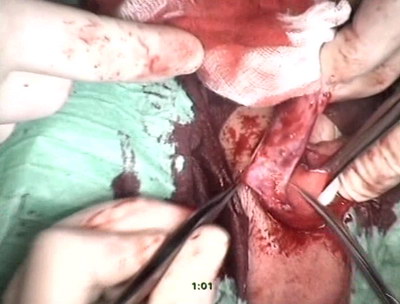

Под комбинированным наркозом произведен U- образный окаймляющий

разрёз под гипоспадическим меатусом от верхушки головки.

Выполнен циркулярный разрез вокруг головки полового члена,

произведено скелетирование ствола, пересечена поддерживающая

связка. В связи с наличием валярной и незначительной боковой

деформации ствола, хорда иссечена после предварительного

выполнения искусственной эрекции, наложены 3 пликационных

шва по методике Nesbit по дорсальной поверхности. На дорсальной